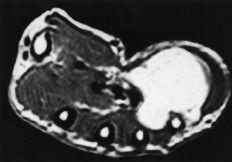

Tumores de estirpe nerviosa

Representan el 7,5% del total (23 casos), diagnosticándose 18 schwannomas y cinco neurofibromas. La edad media de estos pacientes (15 hombres y ocho mujeres) fue de 43 ± 18 años (máximo: 84 y mínimo: 11 años). Siete schwannomas se localizaron en el nervio mediano en la muñeca y dos en el cubital en el canal de Guyon. El resto de los tumores afectaba a nervios digitales colaterales o ramas terminales sensitivas.

El tamaño medio fue de 2,3 * 2,1 cm (máximo: 5 * 6 y mínimo: 0,7 * 0,5 cm). Los que afectaban a los nervios cubital y especialmente al mediano presentaban un test de Tinel positivo sobre la tumoración. No se constataron déficit motores en ningún caso. Un schwannoma del nervio mediano en el túnel carpiano ocasionaba un síndrome compresivo.

La RM presenta un aumento de intensidad de señal homogéneo en las imágenes potenciadas en T2, que contrasta con la ausencia de señal del nervio originario del tumor (Fig. 6).

Los tumores nerviosos son raros, con incidencias recogidas en la literatura del 0,8 al 5% de todos los tumores de la mano.2,6,7,11,12,14,16,23,27,34,35 En las series consultadas los neurofibromas y los schwannomas representan entre el 5 y el 10% de todas las tumoraciones de partes blandas, observándose en la mano un 16% del total.16,23 En nuestra serie se observaron 23 casos, un 7,5% del total, de los cuales 18 eran schwannomas, siete de ellos localizados en el nervio mediano y dos en el cubital. Los schwannomas suelen tener una localización excéntrica en el nervio, siendo rara la afectación de fascículos, y por ello es raro encontrar déficit motores. El schwannoma o neurilemmoma es un tumor benigno procedente de las células de Schwann, encargadas de proporcionar la estructura mielínica al nervio periférico. Su tamaño no suele alcanzar más de 3 cm.2,6,11,12,35 En la serie, los schwannomas originados en el nervio mediano presentaban una característica hiperseñal en T2 en contraste con la ausencia de señal del tronco nervioso del que proceden (Fig. 6). No obstante, la RM sólo pudo definir con claridad que se trataba de un tumor de estirpe neural.10,17,29

Figura 6. Imágenes de RM de un schwannoma del nervio mediano. A y B: Secuencias potenciadas en T1 y T2, respectivamente.